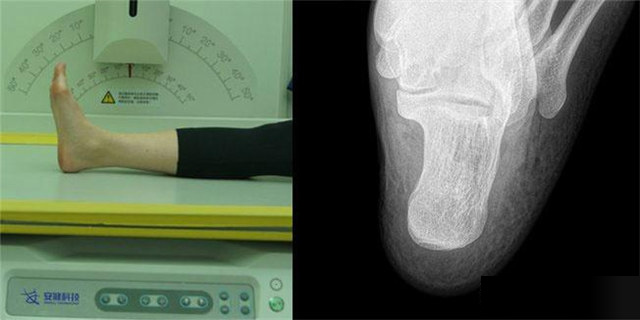

下肢:脛腓骨、踝、足脛腓骨長骨檢查需要包括--側(cè)的關(guān)節(jié)踝關(guān)節(jié)常規(guī)正+外側(cè)位,特殊時可選內(nèi)斜位足常規(guī)前后正位+內(nèi)斜位,外傷鑒定等情況,需要負(fù)重的水平側(cè)位(包括足尖和足跟)跟骨側(cè)位+軸位